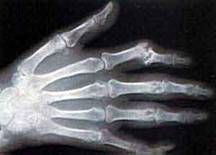

Jako pierwszy odkrył je W.C. Roentgen w 1895 roku. Za swoje odkrycie dostał on Nagrodę Nobla, która to była pierwszą przyznaną Nagrodą Nobla. Zakres długości fal promieniowanie rentgenowskiego po części pokrywa się z zakresem promieniowania gamma (tzw. miękkiego promieniowania gamma). Różnice wynikają z różnych mechanizmów powstawania promieniowania. Otóż promieniowanie gamma jest emitowane w wyniku przejść energetycznych w jądrach atomów. Natomiast promieniowanie rentgenowskie jest inaczej wytwarzane. Wytwarza się je w specjalnych urządzeniach tzw. lampach rentgenowskich, które składają się głównie z elektrod wytwarzających pole elektryczne. Elektrony uwalniane z jednej elektrody pędzą w kierunku drugiej, a gdy do niej docierają wyhamowują. Energia, którą wtedy tracą jest emitowana w postaci fotonów - tzw. promieniowanie hamowania. Widmo tego promieniowania jest ograniczone napięciem doprowadzonym do elektrod. Jednak na tym nie koniec. Elektron po dotarciu do anody może wybić z niej inny elektron (jonizacja), w wyniku, czego w atomie powstaje wolne miejsce, które natychmiast jest zajmowane przez elektron z zewnętrznej powłoki. Energia powstała przy takim przejściu jest emitowana w postaci fotonu o ściśle określonej długości fali - jest to tzw. promieniowanie charakterystyczne. Oba te promieniowanie - promieniowanie hamowania i promieniowanie charakterystyczne składają się na promieniowanie rentgenowskie. Obecnie promieniowanie rentgenowskie oprócz tego, że jest szeroko wykorzystywane w medycynie, to także znalazło zastosowanie w badaniach nad strukturą materii - tzw. rentgenowska analiza strukturalna, oraz w badaniach dotyczących pierwiastkowego składu chemicznego substancji - tzw. rentgenowska analiza widmowa.